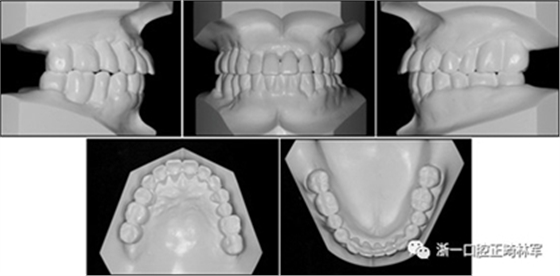

在治療結束時,通過拔除下頜側切牙,間隙閉合和推上頜牙列向遠中,實現(xiàn)了前牙良好的對齊,尖牙I類關系以及合適的覆合和覆蓋?;颊叩膫让婷草喞玫礁纳?,并且她的嘴唇不適得到緩解。下頜右側第二磨牙直立,后牙被修復并恢復穩(wěn)定咬合(圖10和圖11)。牙周治療和牙周病的控制導致牙周袋深度的穩(wěn)定,并且在探測時沒有出血。

圖11.治療后牙齒的石膏模型